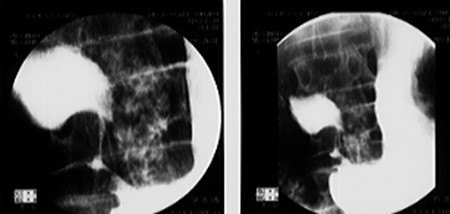

Image radiologie ASP de face

une volvulus de estomac est image de elevation du

diapragme droit avec de distention gastrique marquee |

Image hydroaerique a niveau

au poumon droite : hernie hiatale avec volvulus

gastrique de type organo axiale . |